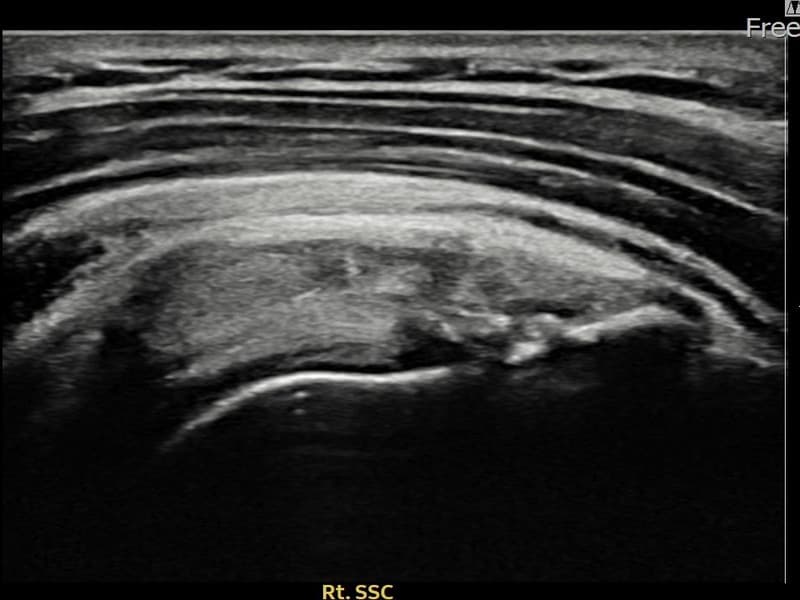

시술 전 초음파 측정 결과 파열 크기는 8.6mm × 4mm (힘줄 두께의 약 45% 결손)로 확인되었습니다. 시술 전 초음파에서 우측 극하근건 부착부의 에코 단절과 힘줄 결손 소견이 확인되었으며, 파열 크기는 8.6mm로 측정되었습니다. 시술 후 초음파에서 부착부 연속성이 회복되고 결손 부위에 재생 조직이 형성된 것이 관찰되었습니다.

30대 후반 남성 환자분으로, 헬스 및 수영을 즐기시다가 우측 어깨 후방 통증이 생겨 내원하셨습니다. 운동 중 어깨에 과도한 외회전 부하가 반복되어 극하근건이 손상된 것으로 판단되었습니다. 초음파 검사에서 극하근건 부착부 부분파열이 확인되었고, 파열 크기는 8.6mm로 의미 있는 손상이었습니다. 수술 없이 초음파 유도 하 축소봉합술을 시행하였으며, 시술 후 보조기 착용 6주와 단계적 재활 운동을 통해 회복을 진행하였습니다. 시술 11주 후 추적 초음파에서 부착부 힘줄 연속성이 회복되어 운동 활동에 복귀하셨습니다.